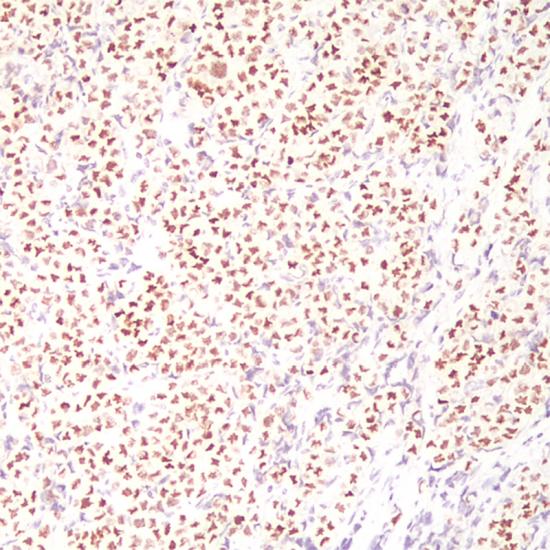

GATA-3

GATA3抗體試劑(免疫組織化學(xué)) 閩廈械備20180095號(hào)

• 陽(yáng)性部位:

細(xì)胞核

• 陽(yáng)性對(duì)照:

乳腺癌

GATA3是一種鋅轉(zhuǎn)錄因子,在許多組織和細(xì)胞類(lèi)型中對(duì)促進(jìn)和引導(dǎo)細(xì)胞增殖、發(fā)育和分化起到重要作用。在乳腺癌和尿路上皮癌高度特異表達(dá)。GATA3表達(dá)于乳腺小葉癌和浸潤(rùn)性導(dǎo)管癌,同時(shí)在乳腺癌中GATA3表達(dá)與ER、PR成正相關(guān)系,與HER-2成負(fù)相關(guān)系。